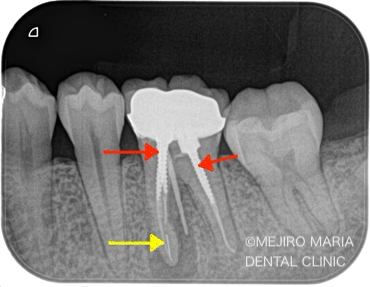

今回の治療はまず、上部の築造体にあるスクリュータイプ(写真1:赤矢印)の除去、ならびに、近心根にある破折ファイル(写真1:黄色矢印)の除去が、治療の際に手間となる工程でした。

築造体や破折ファイルの除去の際に、虫歯を除去するような回転切削器具を無闇に使用すると、余分な歯質を削ってしまい、歯の強度を著しく失う原因や、穿孔(パーフォレーション/穴が開くこと)という偶発事故を起こしたりする危険性が高くなります。そのため、回転切削器具の使用は最小限に抑え、専用の超音波ファイルを用いて除去するのが、理想的な治療であると考えます。

適切な箇所で、適切な器具を選択することが、非常に重要となります。

超音波ファイルを使用し、無事にファイルを除去した後は、通法通りの根管治療を行いました。下記の動画もご参照ください。